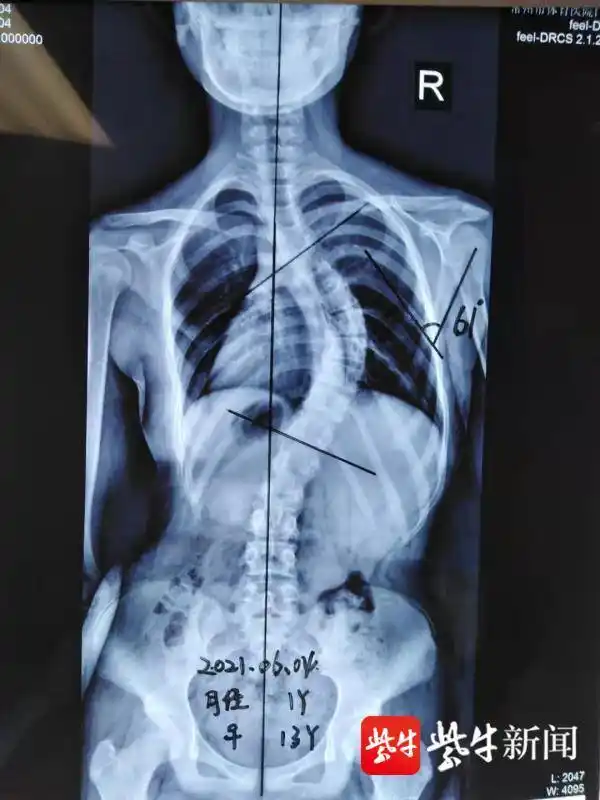

13岁少女肩膀一高一低!专家:当心青少年脊柱侧弯